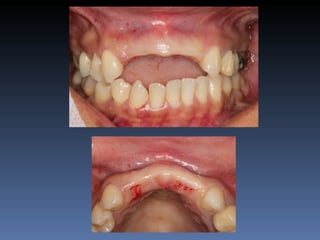

BOX 3 Kátia MariaCavicchia Idade – 43 anos Sexo – Feminino Raça – Caucasiana ASA – II Data- 29-04-2012 Diagnóstico: Desdentado parcial bilateral posterior da mandíbula. Plano de tratamento: Reabilitação bilateral posterior mandibular com instalação de 6 implantes endo- ósseos, para reabilitação protética fixa.

• 158.

Zona 4.4, 4.5,4.6 Zona 3.5, 3.6, 3.7